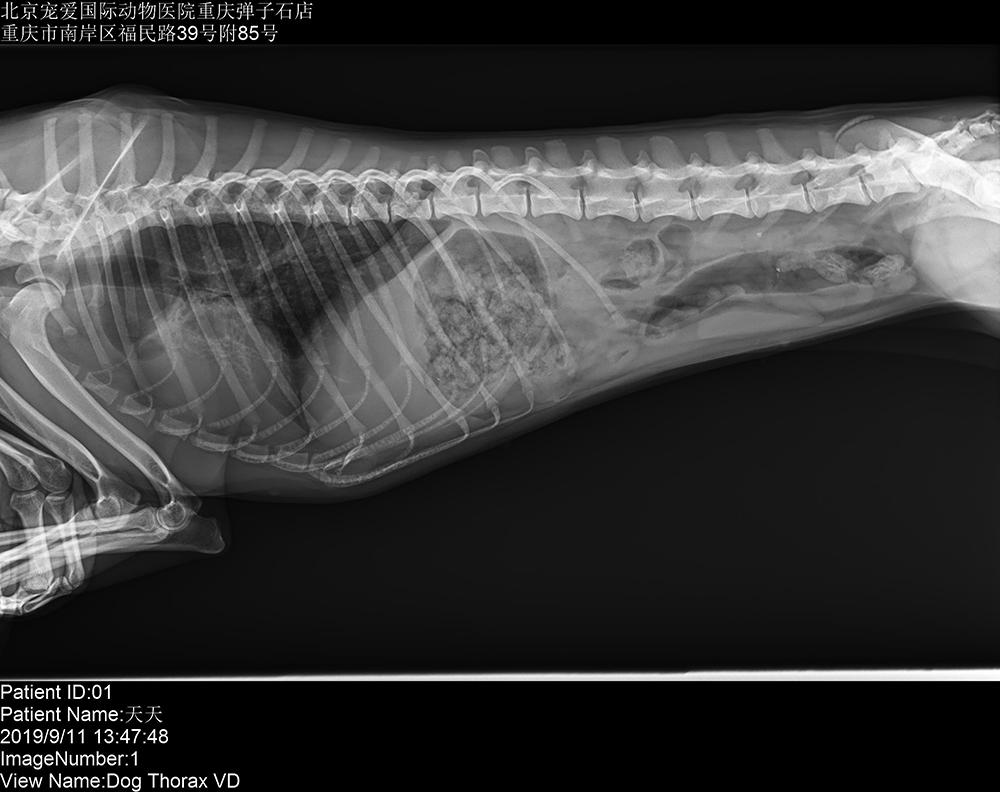

寵愛國(guó)際動(dòng)物醫(yī)院重慶彈子石分院 2019/9/16 上一篇: 重慶侏羅紀(jì)動(dòng)物醫(yī)院涪陵分院 下一篇: 寵愛國(guó)際動(dòng)物醫(yī)院重慶江與成分院